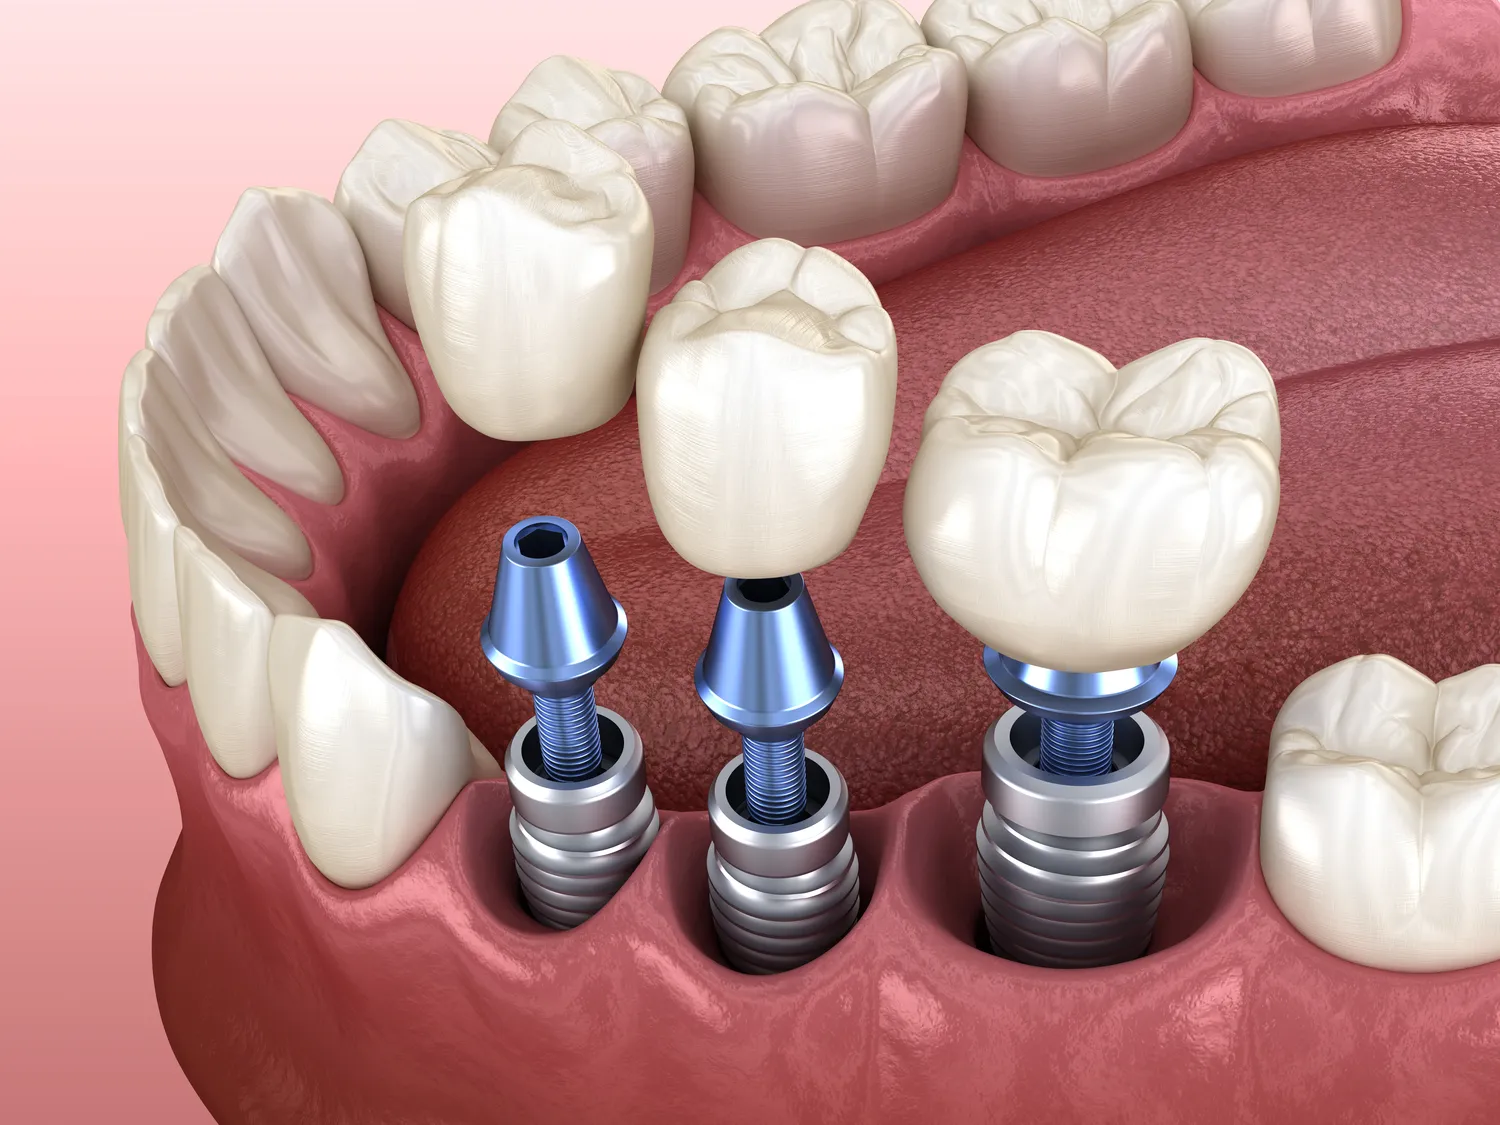

Implanty zębów to nowoczesne rozwiązanie, które zyskuje coraz większą popularność wśród pacjentów potrzebujących uzupełnienia brakujących zębów. Jednym z najczęściej zadawanych pytań przez osoby rozważające tę formę leczenia jest to, jak długo wytrzymują implanty zębów. W rzeczywistości trwałość implantów zależy od wielu czynników, takich jak jakość materiału, technika chirurgiczna, a także higiena jamy ustnej pacjenta. Właściwie przeprowadzony zabieg oraz odpowiednia pielęgnacja mogą znacząco wydłużyć żywotność implantu. Z reguły implanty stomatologiczne wykonane z tytanu mogą służyć pacjentom przez wiele lat, a nawet przez całe życie, jeśli są odpowiednio pielęgnowane. Ważne jest również regularne kontrolowanie stanu zdrowia jamy ustnej oraz wykonywanie przeglądów u stomatologa, co pozwala na wczesne wykrycie ewentualnych problemów związanych z implantami.

Trwałość implantów zębów jest uzależniona od wielu czynników, które warto wziąć pod uwagę przed podjęciem decyzji o ich wszczepieniu. Po pierwsze, kluczowe znaczenie ma jakość materiału użytego do produkcji implantu. Tytan jest najczęściej stosowanym materiałem ze względu na swoje właściwości biokompatybilne oraz odporność na korozję. Po drugie, technika chirurgiczna oraz doświadczenie lekarza mają ogromny wpływ na sukces całego zabiegu. Właściwe umiejscowienie implantu oraz jego stabilizacja w kości szczęki są niezbędne dla długotrwałego efektu. Kolejnym istotnym czynnikiem jest higiena jamy ustnej pacjenta. Regularne szczotkowanie zębów, nitkowanie oraz wizyty kontrolne u stomatologa są kluczowe dla zapobiegania infekcjom i innym problemom zdrowotnym, które mogą wpłynąć na trwałość implantu.

Pomimo wysokiej skuteczności i trwałości implantów zębów mogą wystąpić pewne problemy związane z ich użytkowaniem. Jednym z najczęstszych kłopotów jest infekcja wokół implantu, znana jako periimplantitis. Może ona prowadzić do stanu zapalnego tkanek miękkich oraz utraty kości wokół implantu, co w skrajnych przypadkach może wymagać jego usunięcia. Innym problemem mogą być reakcje alergiczne na materiały użyte do produkcji implantu, chociaż są one rzadkie i dotyczą głównie osób uczulonych na tytan lub inne metale. Ponadto niewłaściwe umiejscowienie implantu lub brak odpowiedniej ilości kości może prowadzić do jego niestabilności i bólu podczas żucia. Dlatego tak ważne jest przeprowadzenie dokładnej diagnostyki przed zabiegiem oraz wybór doświadczonego specjalisty.

Proces gojenia po wszczepieniu implantu zęba jest kluczowym etapem całej procedury i może trwać od kilku tygodni do kilku miesięcy w zależności od indywidualnych predyspozycji pacjenta oraz techniki chirurgicznej zastosowanej przez lekarza. Po zabiegu pacjent może odczuwać dyskomfort lub ból w okolicy wszczepionego implantu, dlatego lekarz często zaleca stosowanie leków przeciwbólowych oraz środków przeciwzapalnych. Ważne jest również przestrzeganie zaleceń dotyczących diety; przez pierwsze dni po zabiegu zaleca się spożywanie miękkich pokarmów oraz unikanie gorących napojów i alkoholu. W ciągu kilku tygodni następuje proces osteointegracji, czyli integracji implantu z kością szczęki; to kluczowy moment dla stabilności implantu. Regularne wizyty kontrolne u stomatologa pozwalają na monitorowanie postępu gojenia oraz wykrycie ewentualnych komplikacji na wczesnym etapie.